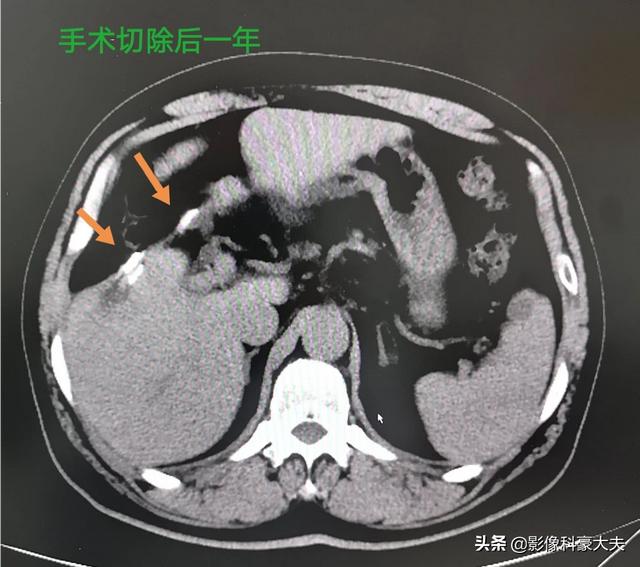

B型慢性肝炎の患者さんで、健康診断で小さな肝臓がんが見つかりました。手術が間に合わなければ、長くて半年で進行癌に進行してしまいます。現代の先端機器のおかげで、この患者さんは発見も手術も間に合い、1年以上経過していますが再発はありません:

いい風は空に届く!